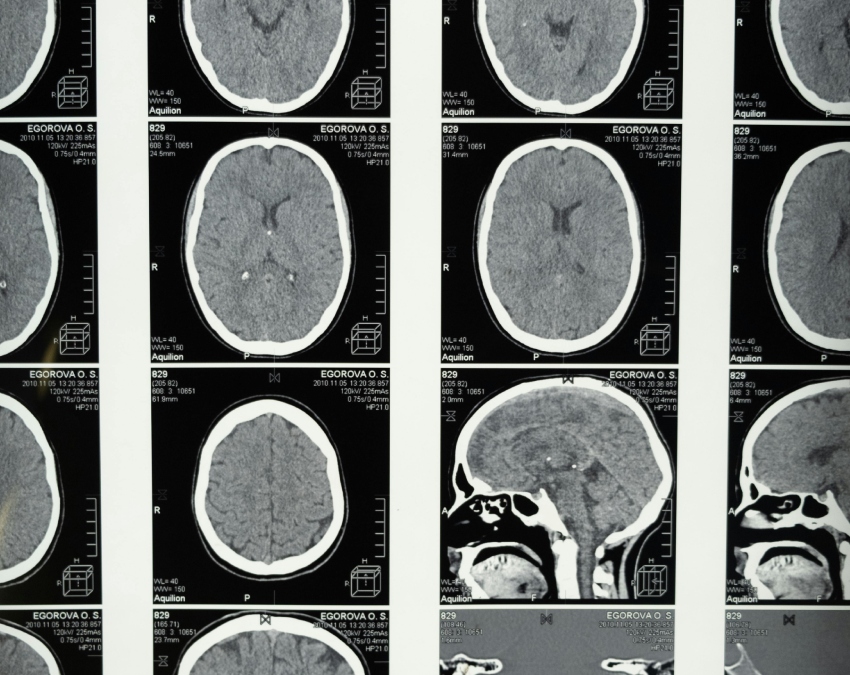

ब्रेन ट्यूमर से पूरी तरह बचाव का कोई पक्का तरीका नहीं है, लेकिन सही लाइफस्टाइल और कुछ सावधानियां अपनाकर इसके खतरे को काफी हद तक कम किया जा सकता है. जैसे-बार-बार एक्स-रे न कराना, कीटनाशक, इंडस्ट्रियल केमिकल्स और टॉक्सिक पदार्थों से बचाव, हेल्दी डाइट को अपना और डॉक्टर की रेगुरल जांच कराने से इस समस्या को काफी हद तक कम किया जा सकता है.

एक्सपर्ट के मुताबिक जिन लोगों की फैमिली हिस्ट्री है, रेडिएशन का ज्यादा एक्सपोजर है, बढ़ती उम्र, खतरनाक केमिकल्स के संपर्क में रहना, कमजोर इम्युनिटी वाले लोगों को ब्रेन ट्यूमर का खतरा ज्यादा होता है.